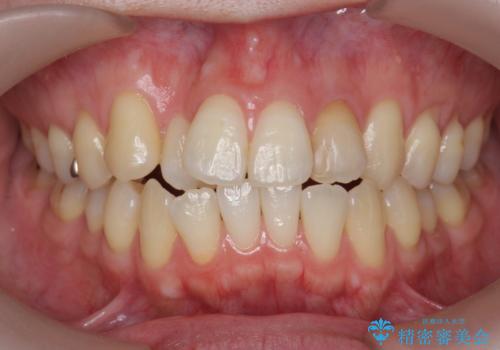

【非抜歯】インビザラインで正しい噛み合わせを

前歯のガタつきを治したい 翼状捻転マウスピース矯正

【インビザライン】がたつきをマウスピースできれいにしたい